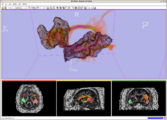

Intraoperative navigation experiments integrate slicer3 with the commercial BrainLab system and Yale's BioImageSuite software.